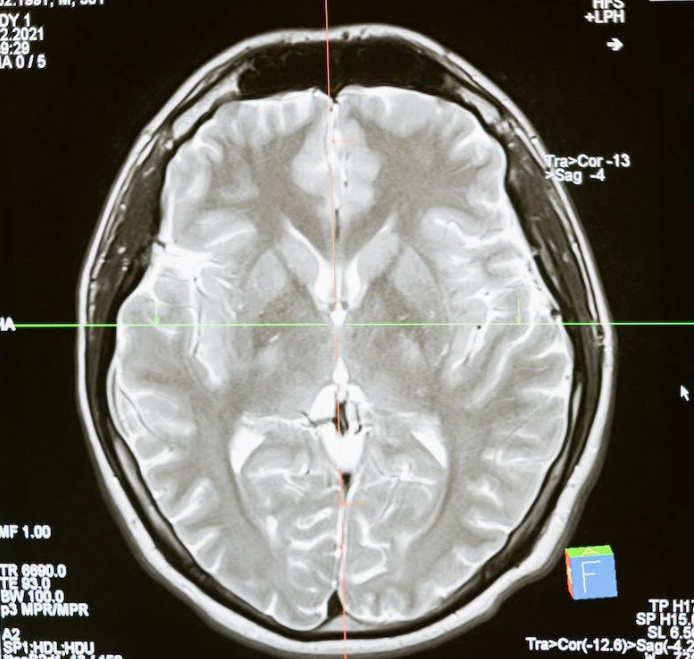

뇌는 우리 몸의 제어 중심이자 가장 중요한 기관 중 하나입니다. 그러나 때로는 다양한 위험으로 인해 뇌 세포가 손상을 입을 수 있습니다. 뇌 세포의 손상은 충격의 정도, 유형, 뇌 상태, 그리고 개인적인 요인에 따라 다양하게 나타납니다. 이 블로그 글에서는 뇌 세포의 손상과 관련된 주요 요소들을 자세히 살펴보고, 어떻게 뇌 손상을 예방하고 치료하는 방법에 대해 알아보겠습니다.

충격의 세기가 뇌 세포에 미치는 영향은 상당히 중요합니다. 강력한 충격은 뇌 세포에 상당한 손상을 입힐 수 있으며 이러한 충격은 교통사고나 폭발과 같은 상황에서 발생할 수 있습니다. 이러한 상황에서는 뇌 세포의 손상을 예방하기 위해 안전한 조치를 취하고 안전장비를 착용해야 합니다. 더 구체적으로, 교통사고 예방을 위해 안전벨트 착용과 안전 운전 습관을 유지하는 것이 중요합니다. 또한, 폭발이 발생할 가능성이 있는 환경에서는 안전 절차를 준수하는 것이 중요합니다.

충격이 뇌의 특정 부분에 영향을 미치면 그 부위와 관련된 뇌 세포의 기능에 영향을 줄 수 있습니다. 뇌는 여러 부분으로 구성되어 있으며 각 부분은 특정한 기능을 수행합니다. 따라서 특정 부위에 손상이 발생하면 그 부위와 관련된 기능에 문제가 발생할 수 있습니다. 이를 예방하기 위해 강력한 충격을 피하고 안전한 환경을 조성하는 것이 중요합니다.

충격이 얼마나 오래 지속되는지도 중요한 역할을 합니다. 긴 시간 동안 지속되는 충격은 뇌 세포에 더 큰 손상을 입힐 수 있으며, 이는 뇌 건강에 부정적인 영향을 미칠 수 있습니다. 따라서 위험한 상황에서는 빠르게 대응하고 충격 지속 시간을 최소화하는 것이 중요합니다. 충격이 지속되는 동안 안전한 위치로 이동하거나 구호 요청을 하여 도움을 받는 것이 중요합니다.

뇌 세포의 손상을 피하고 뇌 건강을 지키기 위해서는 안전을 최우선으로 고려해야 합니다. 안전장비를 착용하고 위험한 상황에서는 예방 조치를 취해야 합니다. 또한 뇌 손상의 초기 징후가 나타날 경우 즉각적인 의료 진료가 필요하며, 이러한 예방과 신속한 치료 조치는 뇌 세포 손상을 최소화하는 데 도움이 됩니다.